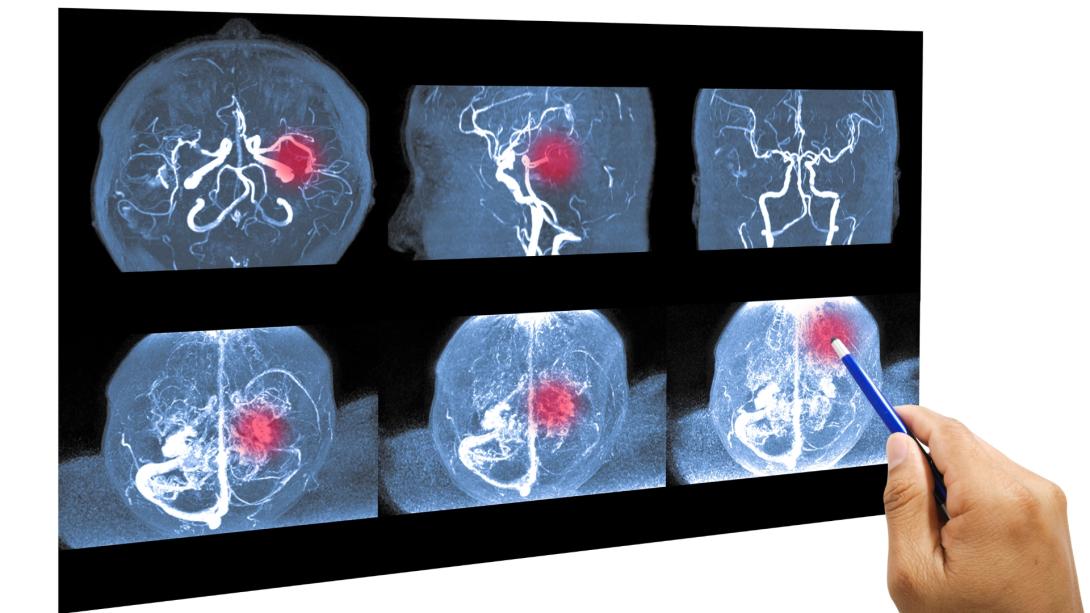

Xuất huyết não là một trong những biến chứng nguy hiểm nhất của bệnh lý tăng huyết áp. Khi áp lực máu lên thành mạch quá lớn khiến mạch máu bị vỡ, máu sẽ tràn vào mô não gây tổn thương nghiêm trọng. Đây là tình trạng cấp cứu y khoa khẩn cấp, đòi hỏi sự nhận biết sớm và can thiệp tức thì để giảm thiểu nguy cơ tử vong và di chứng tàn phế.

Tăng huyết áp kéo dài nếu không được kiểm soát tốt sẽ làm thành mạch máu bị xơ vữa, trở nên mỏng và giòn. Khi có một đợt huyết áp tăng cao đột ngột (do gắng sức, căng thẳng, hoặc thay đổi thời tiết), các mạch máu nhỏ trong não không chịu nổi áp lực và bị vỡ ra, gây chảy máu não.